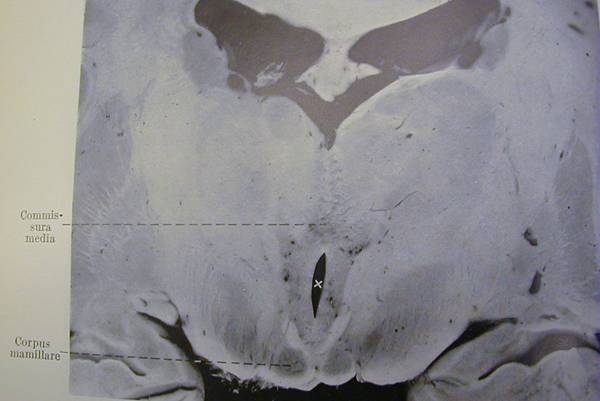

- Damage in the mammillary bodies caused by chronic alcohol intoxication. From Kant (1933).

Kant (1933) reported clinical and autopsy findings in

17 more cases of chronic alcohol use, and he

reviewed the literature to date, 50 years after

Wernicke's original report. Figures 11 and 16 are

photos from Kant's article (reproduced here with

permission from Springer Verlag). Figure 11 is still

an excellent example of the petechial (flea-bite size)

hemorrhagic damage first reported by Gayet and

Wernicke. Like Gamper, Kant found the mammillary

bodies most seriously damaged, but also noted the

important and consistent involvement of the inferior

colliculi.

Figure xx: Damage in the mammillary bodies (Corpus mamillare) caused by

chronic alcohol intoxication. From Kant (1933).